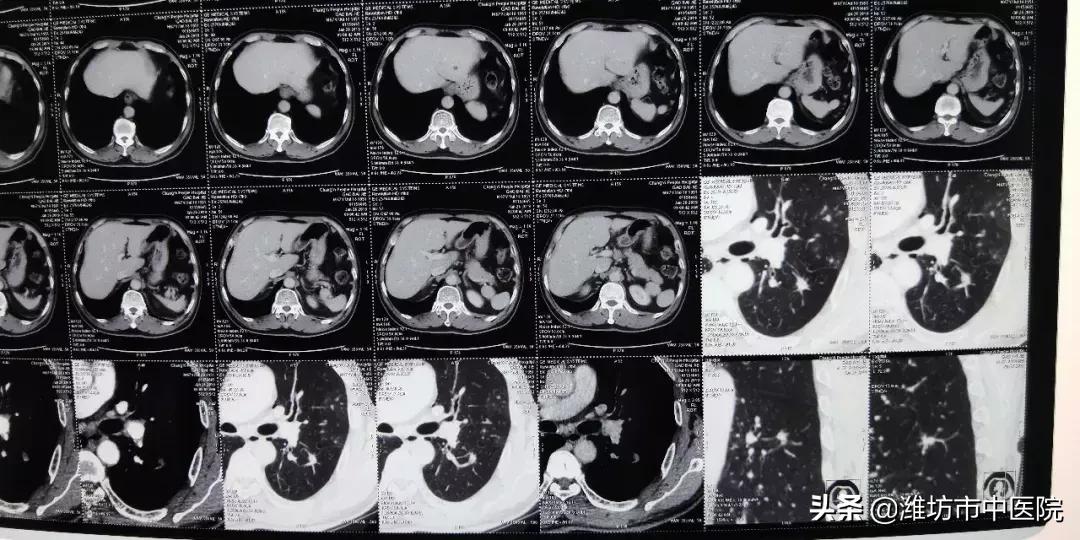

66岁的高先生半月前因咳嗽、咳痰于当地医院行CT检查发现肺部感染、左肺下叶占位,经抗感染10天后复查胸部增强CT示:肺部感染吸收,左下肺占位无明显变化,考虑恶性肿瘤不除外。

胸部CT检查显示左肺下叶病变